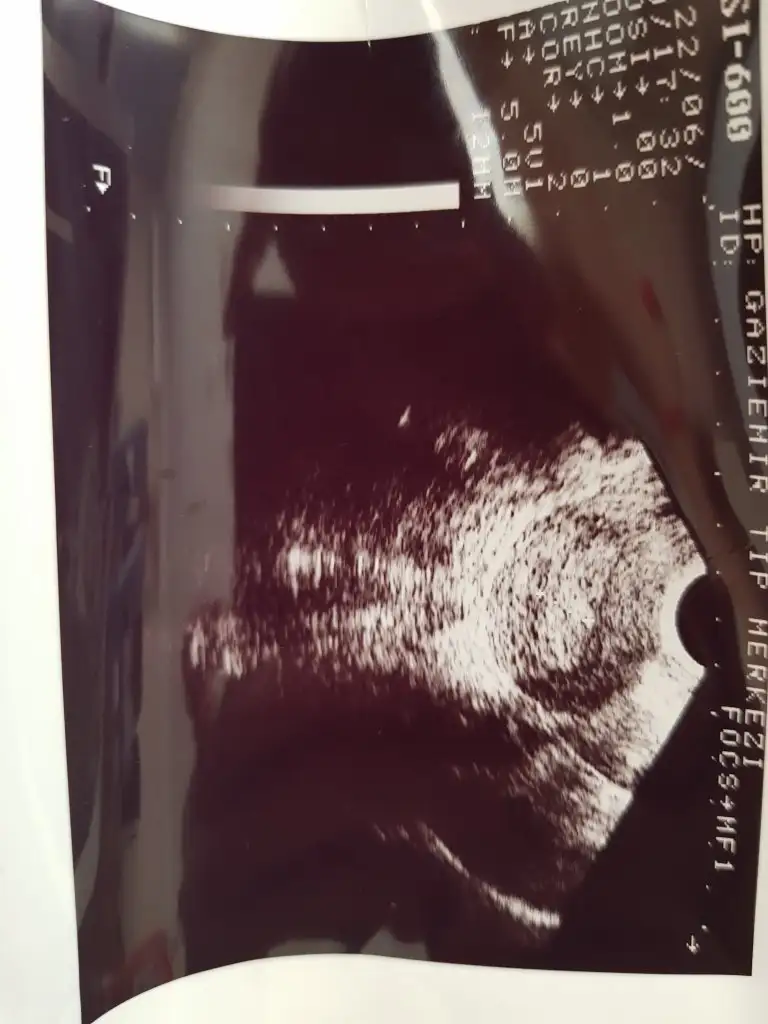

Merhaba eşimle hamileik için bu ay denemeler yaptık bir kez de değil hani yumurtlamadan önce sonra yumurtlama zamanı falan baya denedik yani olur diye düşünmüştüm açıkçası hattâ birkaç belirti de vardı fakat tüm testlerim hep negatif cikti kan vermistim oda negatif çıktı 1.20 çıkmıştı 2 gjn once kanama oldu leke şeklinde siyahımsı kahverengimsi değişik yerlesme kanaması sandım çünkü adetime 5 gün vardı ertesi gün bi baktım baya akışkan olmuştu ki karnım da ağrımaya başlamıştı kasiklarim falan bugün 3. Gün az önce doktordan geldim kistten falan şüphelendim çünkü seneler önce bir doktor bana cikolata kistjn var demisti sknra baska bir doktora gitmistim yok dedi bol su ic demisti o gunden beri gitmedim taki evlendim simdiee cocyk istoyiruz ilk defa bu ay denedik bu ayi ful degerlendirdik fakat 5 gun erken kanama basladi regl oldum bugjn 3. Günüm doktora gitmek istedim gittik kist icin doktor yok dedi fakat rahmin 12 m dedi normalde çok ince olması gerek dedi bu kanama adet kanaması değil dedi başka dedi hamilelik falam olabilirmi dedim olabilir dedi fakat adetim şuan bildiğiniz hala kanama var ve bu bende normal adetten farklı olarak bir kanama ilk başlarda ağrısız olmuştu su gibiydi akışkan pihtisizdi 3-4 aydir böyle arada pıhtı oluyor bende regl oluyorum saniyordum ama baska bisey varmis galiba bence rahim kalinlasmasi bu aya ozel bisey degil gibi acaba hamile kaldim sonra icimde olmadi falanmi ya kafamda bir sürü şey var baya taktım adet kanaması değil dedi özele gitmiştik kan testi istedi oda fiyat baya yüksek gelince devlete gidelim dedik bakalım tekrar doktora gidicem korkuyorum inşAllah kötü bisey yoktur böyle bi durum yaşayan varmı yada bilgisi olan acil yardımcı olurmusunuz lütfen kendimi hiç iyi hissetmiyorum inşallah bilgisi olan vardır şimdiden çok sagolun  buarada ikili fotoğraf yumurtalıklarımın onlar iyi dedi doktor tekli olan fotoğraf rahmimin onada kalınlaşma var dedi fakat ben fotoğrafta yuvarlak bisey görüyorum ne olabilir acaba ?Yarın adet günüm umarım olmam yazarım hamile kaldiysam o ara kanamanın olması büyük şans dedi doktor hemen değerlendirin dedi yaptık bakalım inşallah